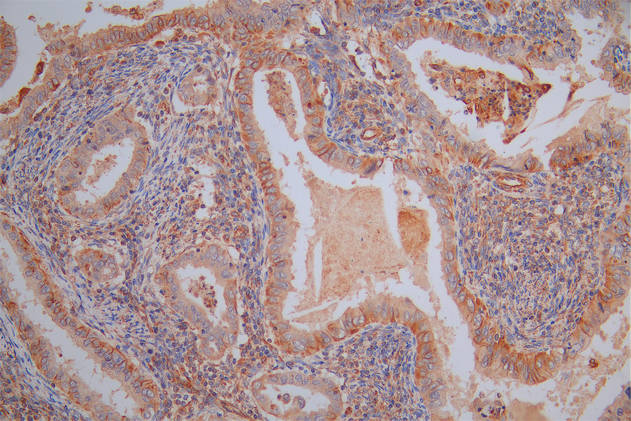

Immunohistochemistry of paraffin-embedded human breast cancer using CSB-PA854079ESR1HU at dilution of 1:100

Immunohistochemistry of paraffin-embedded human placenta tissue using CSB-PA854079ESR1HU at dilution of 1:100

Immunohistochemistry of paraffin-embedded human pancreatic tissue using CSB-PA854079ESR1HU at dilution of 1:100